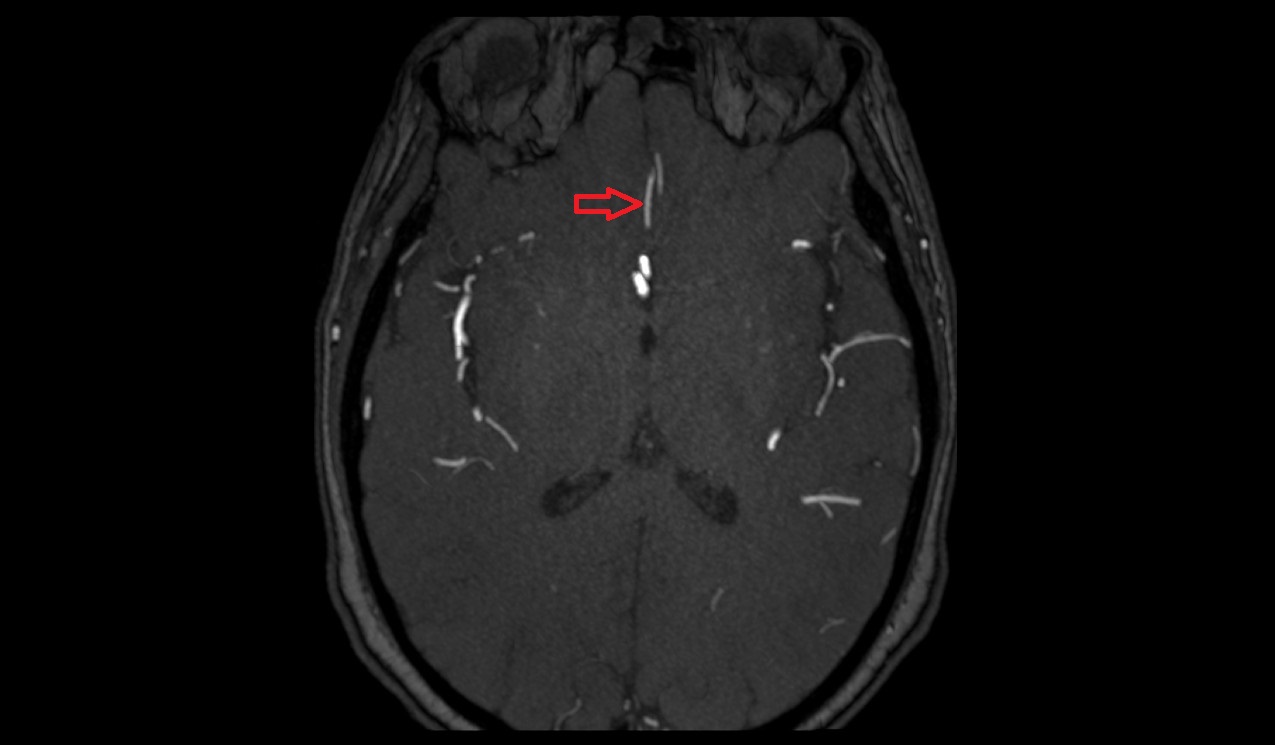

- Middle cerebral artery

- Middle cerebral artery horizontal segment (M1)

- Middle cerebral artery insular segment (M2)

- Middle cerebral artery opercular segment (M3)

- Middle cerebral artery cortical segment (M4)